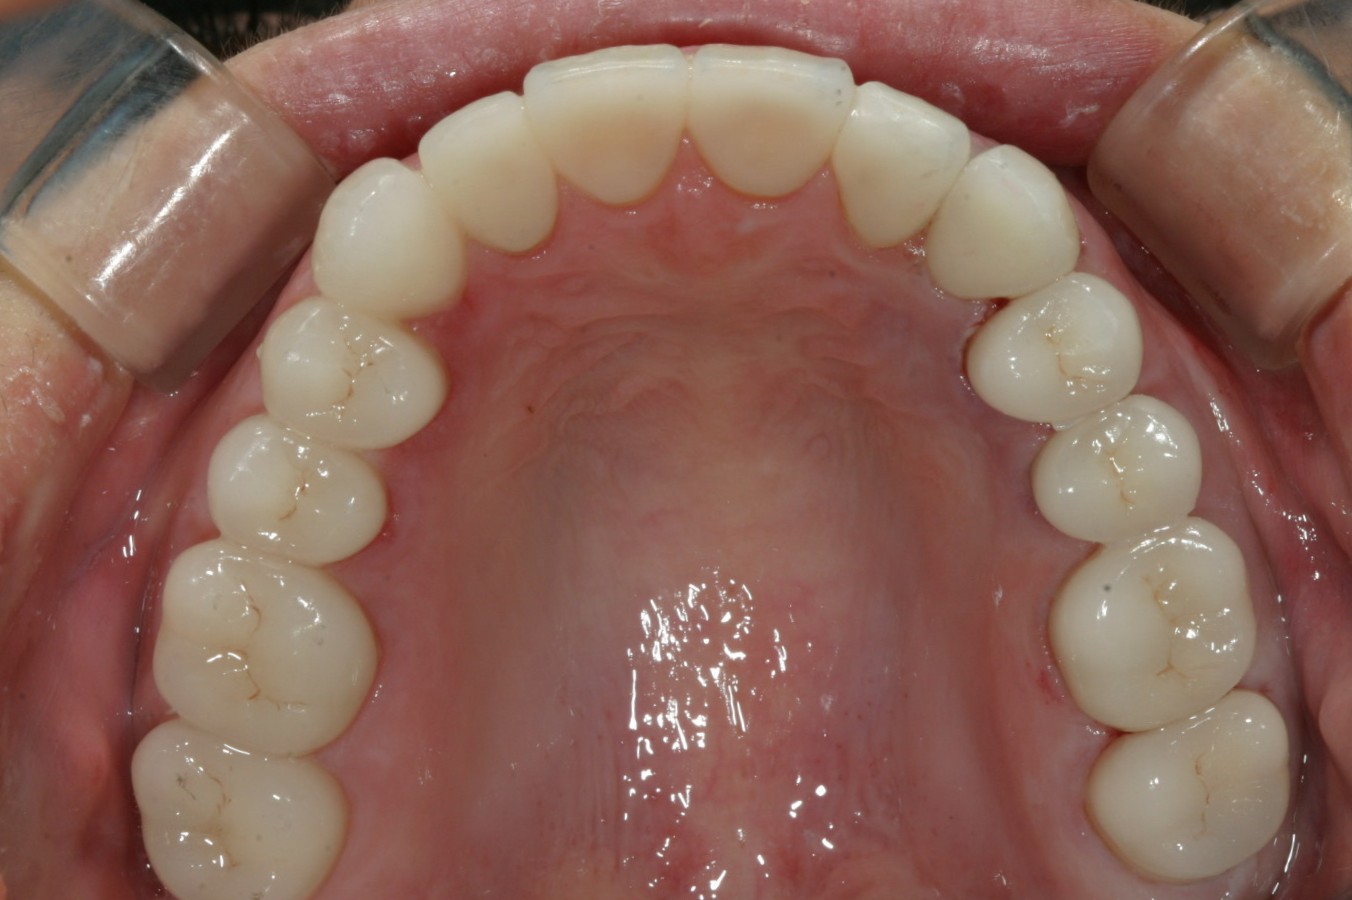

上顎全部ジルコニアクラウンで適正な高さを与え修復しました。